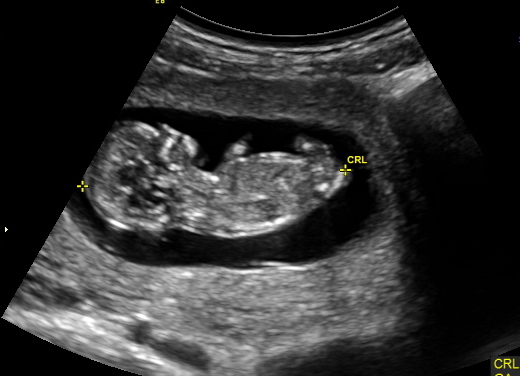

Slight boy lean x

Thank you for responding. I think top looks boy but the second pick has 3 lines which makes me think girl. Confusing. Again, thank you for your guess.

3 lines doesn't say anything on a side shot at 12 weeks. You need a potty shot at 15/16 weeks. Top one got me leaning boy but absolutely not sure!!

i think its probably a boy especially at 12 weeks gestation BUT nubs are never 100%, i hope you get what you want

It's the blob on the top that makes it look boy BUT there is so much going on the blob area that I would not be surprised if it turned out a girl.